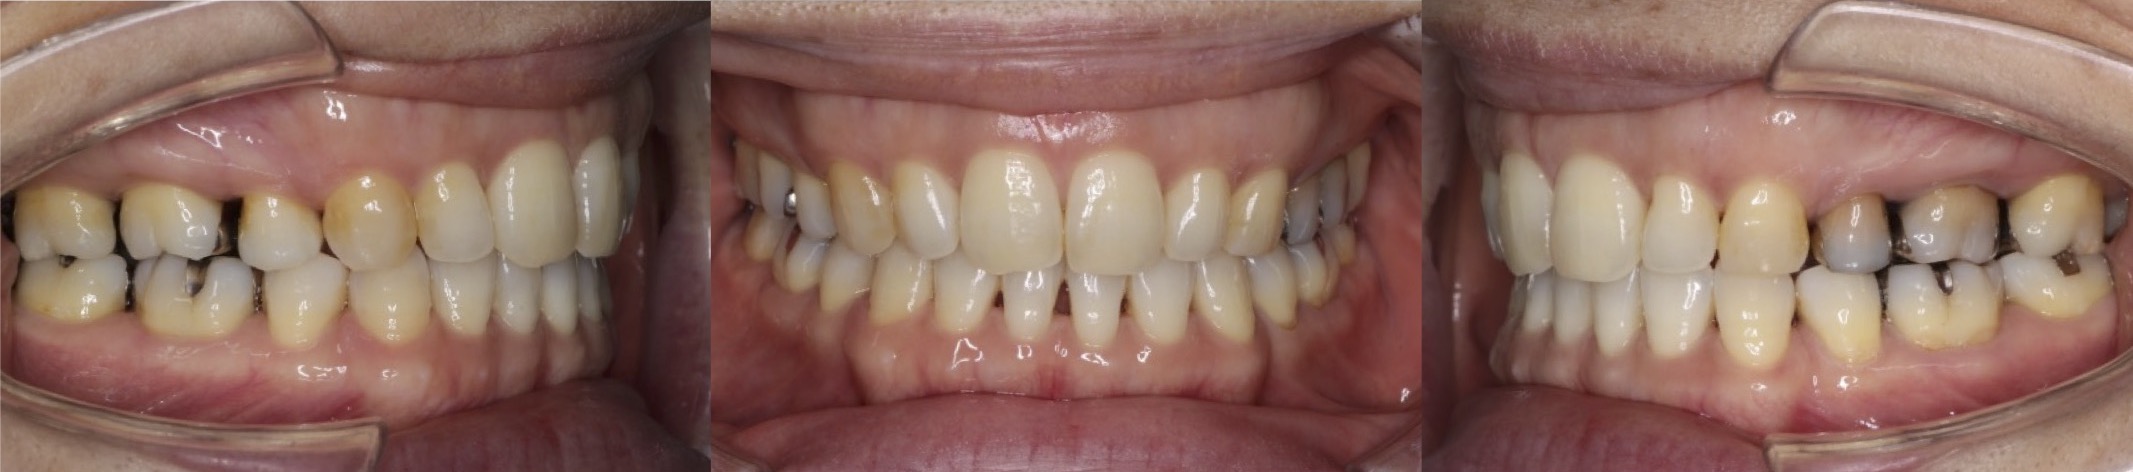

42歳女性・重度叢生・マウスピース装置

ミドルエイジの矯正治療では、できる限り抜歯を併用しないのですが、このように重度のがたつきがある場合は、抜歯を併用します。

<症例概要>

主訴:がたつき

年齢・性別:40代女性

住まい:千葉県佐倉市

症状:叢生・下顎右辺・右II級

抜歯:上左右4番・左下4番(計3本)

治療方針:抜歯空隙閉鎖

治療装置:マウスピース型矯正装置(アライナー装置)

治療期間:2年0か月

アライナー枚数:34+27-14ステージ

リテーナー:上フィックスタイプ+プレートタイプ

治療費用:990,000(税込)

代表的副作用:痛み・治療後の後戻り・歯根吸収・歯髄壊死・歯肉退縮

▶︎その他の副作用

【治療シミュレーション】

上の抜歯空隙に、ゆっくりと確実に犬歯を移動させます。

※マウスピース型カスタムメイド矯正歯科装置は完成物薬機法対象外の矯正装置であり、医薬品副作用被害救済制度の対象とはならない可能性があります。